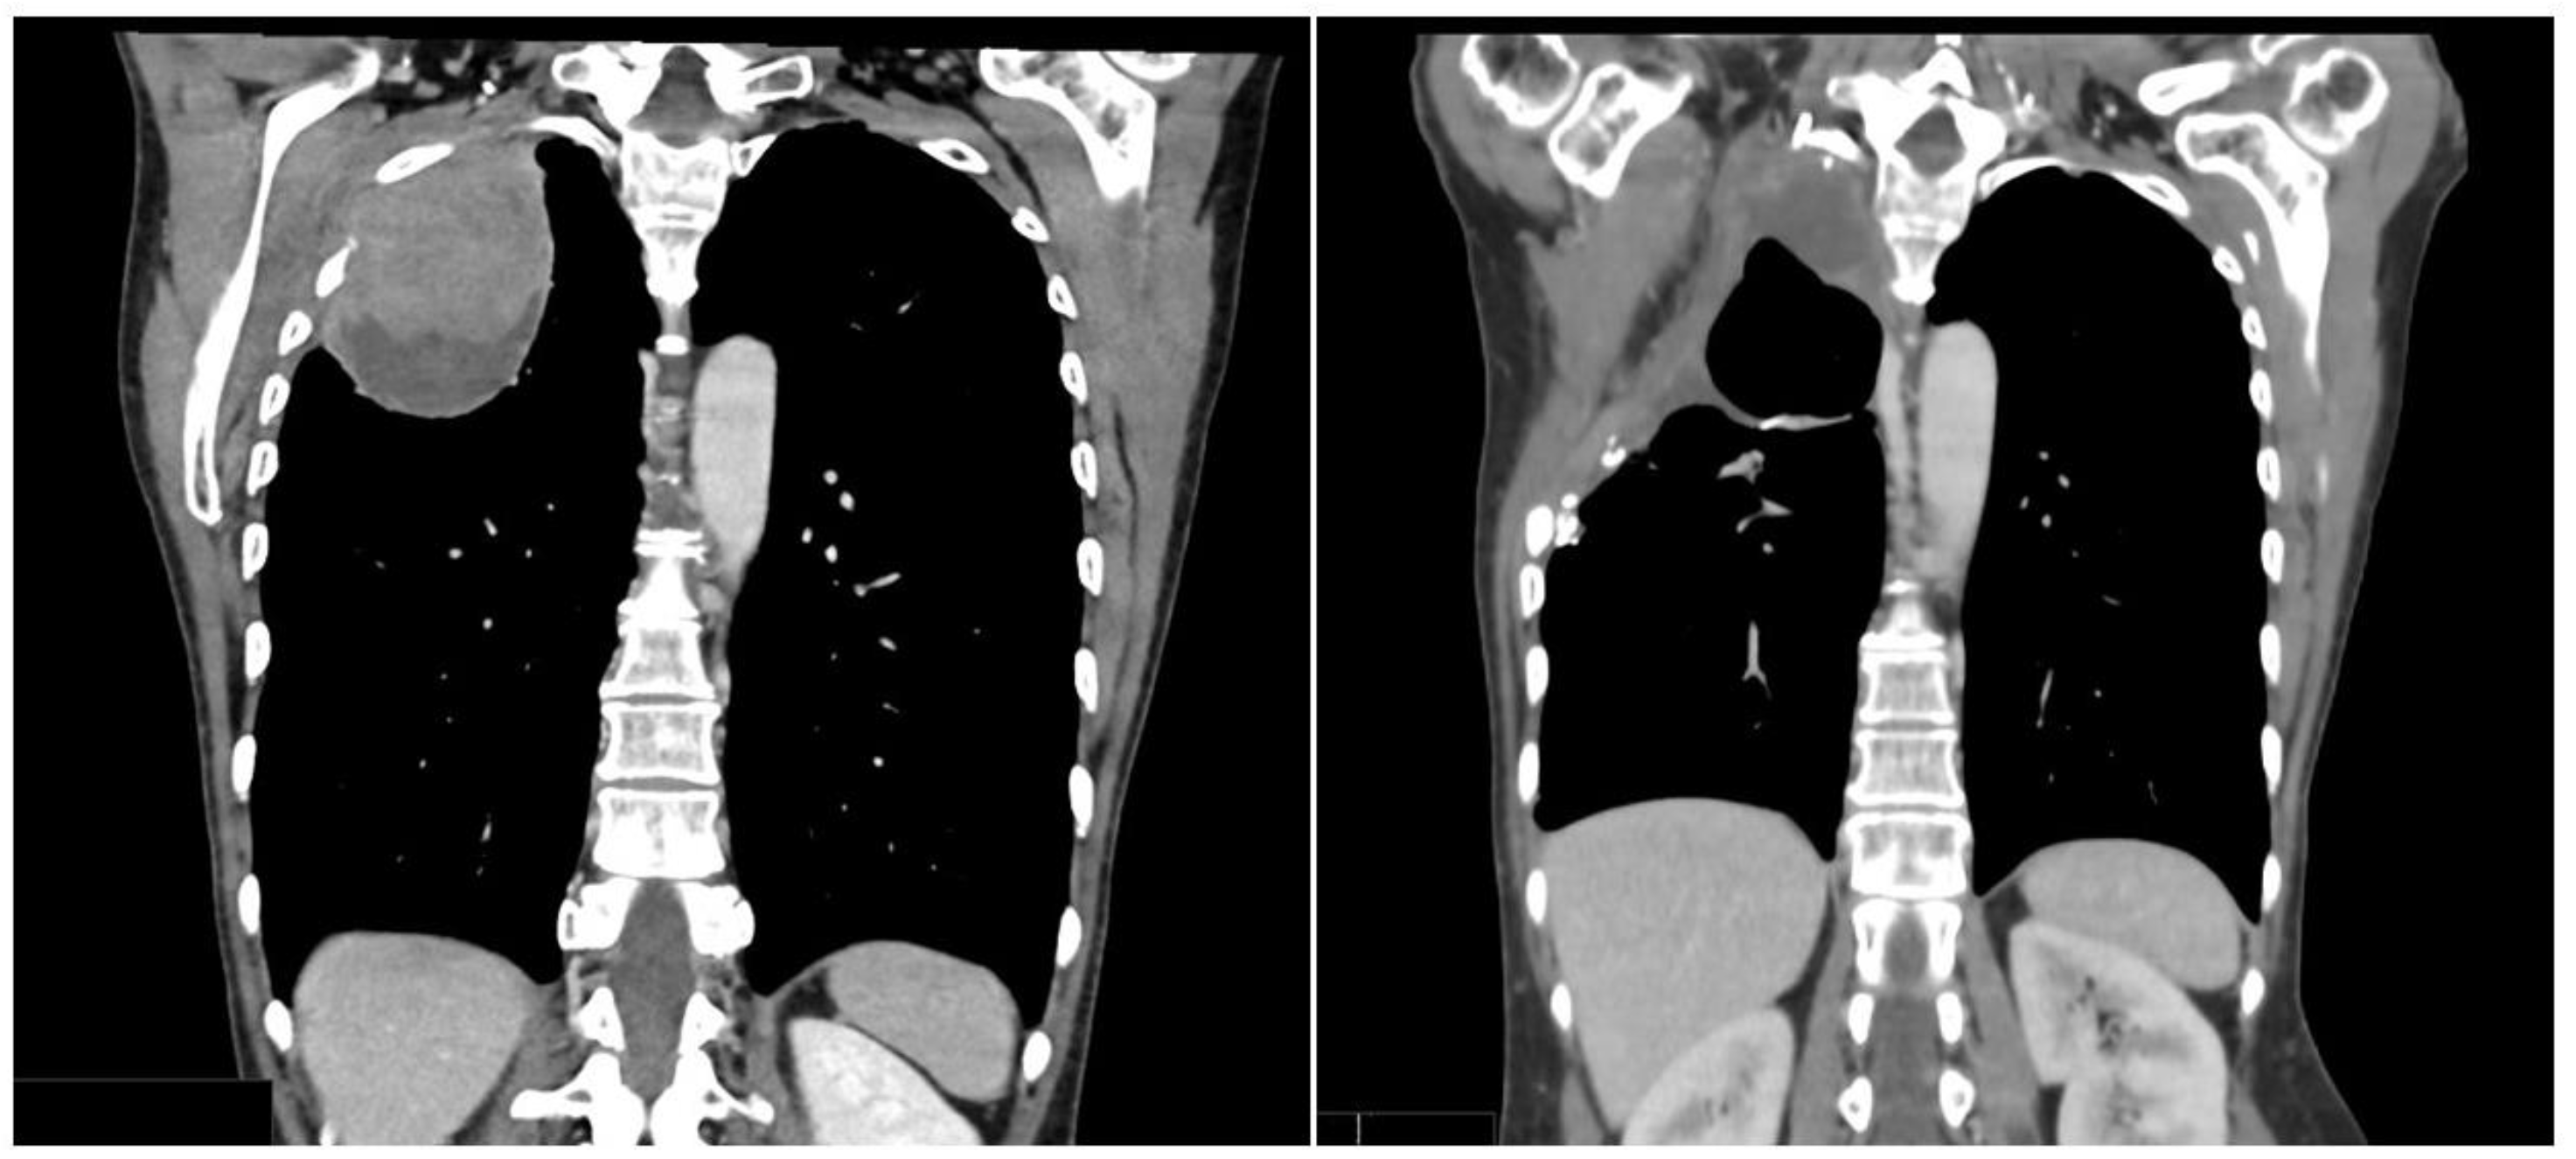

3.1. Case 1

3.2. Case 2

3.3. Case 3